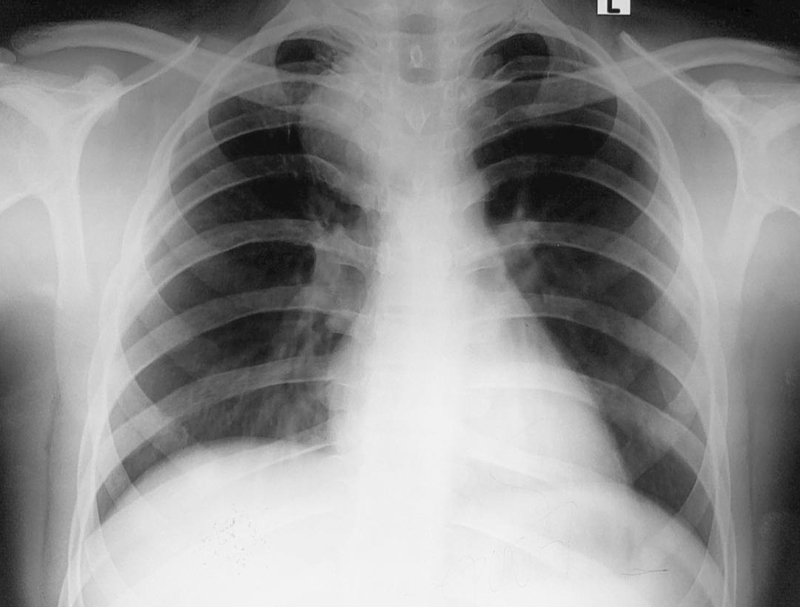

How We Diagnose Bronchogenic Cysts

Our specialists use advanced imaging and diagnostic methods such as:

• CT Scan

• MRI

• Bronchoscopy

• Ultrasound (in certain cases)